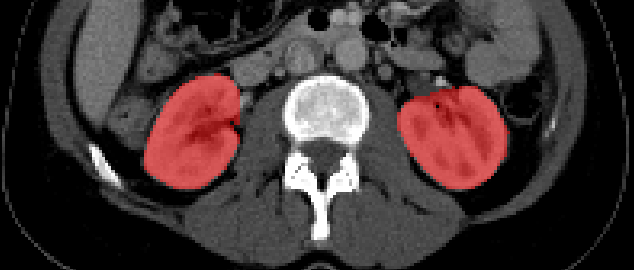

The left and right kidney differ slightly in size, shape, and spatial location [8] (see fig 1). Thus, we propose a proxy task to classify whether a given pair of kidneys belong to the same side. To accomplish this, the network needs to develop an understanding of the structure and sizes of the kidneys. We hypothesize that this knowledge is useful in the main task of kidney segmentation. We begin by dividing the abdominal CT volume into two halves along the sagittal plane, thus obtaining one kidney in each half. We observed that when complete halves of the CT scan are passed, the network learns to perform this task very easily, based on the spatial location of the two kidneys. In such cases when the task is too easy and does not require considerable semantics, it is observed that transfer learning to do a main task is poor. It is desirable to force the network to learn to do the task, based only on the shape and size, rather than the spatial location. Accordingly, each kidney section is extracted using the kidney annotation mask and a fixed region of 64x112x112 pixels around the kidney is passed to the network.

Refer to caption

Fig. 1: Axial view of right and the left kidney in a CT volume